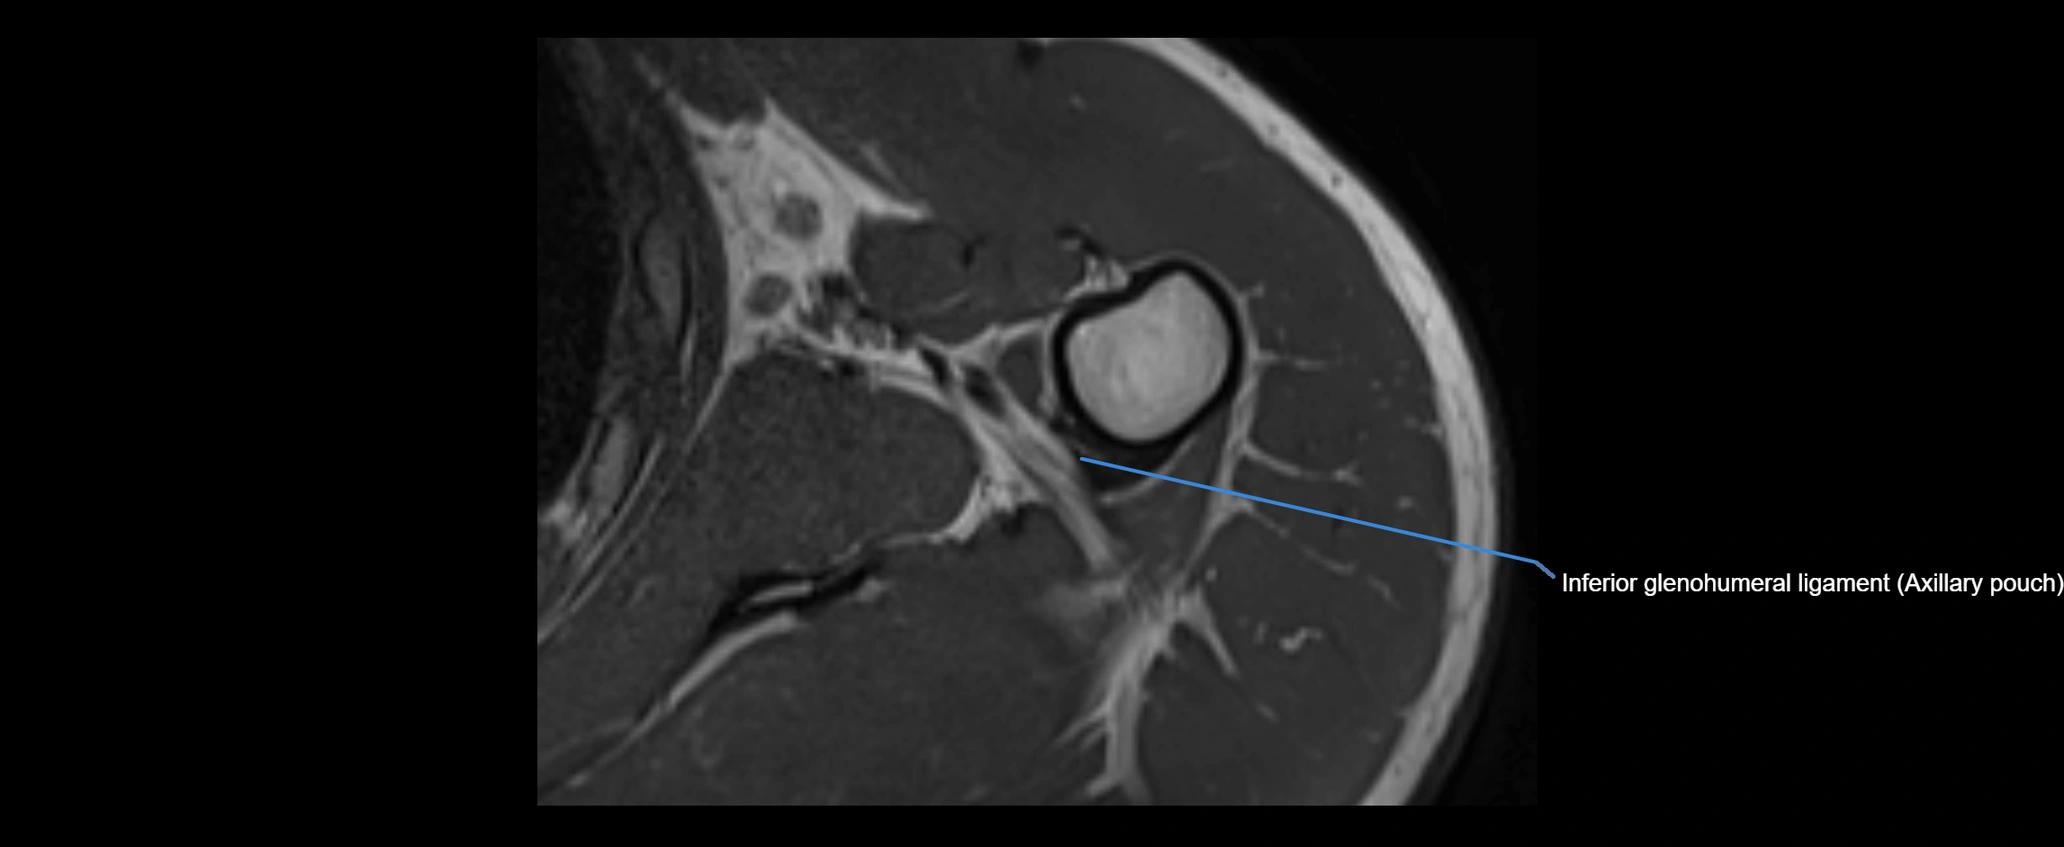

MRI images

image